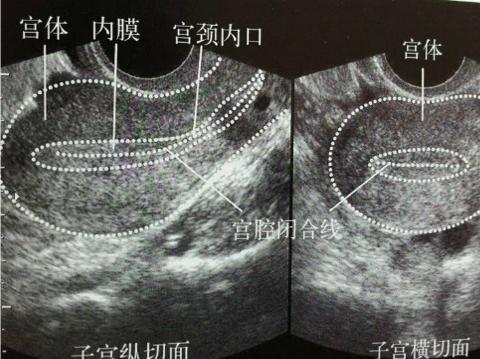

首先,卵泡的发育与月经周期的长短有关,并且是一个动态过程。既然是一个动态过程,就不能以一次B超结果为准。以你目前的月经周期天数及B超结果,没有看出有不正常的情况。

其次,内膜的发育与体内激素水平及卵泡发育有关,也是一个动态过程。目前的情况没有特别不好,建议继续观察。

子宫内膜的厚薄和形态,涉及到的是子宫内膜容受性的问题。胚胎着床的成功, 关键在于胚胎发育必须与子宫内膜同步化。所以除了胚胎的质量外, 子宫内膜容受性也起着至关重要的作用。

作为患者,不要纠结于子宫内膜绝对值的厚与薄,不要纠结于子宫内膜一个或两个周期的好与坏。判断子宫内膜,一般有两个标准,即纵向标准和横向标准。横向标准是与临床上所遵守的,公认的正常标准比较;纵向标准是与自己以往治疗周期所比较。对于子宫内膜较薄的患者,经过采取措施,多个周期未达到理想标准,不能作为放弃移植的理由。作为患者,对于如何调整子宫内膜到最佳状态无能为力,有所作为的是调整心态,保持良好的精神面貌,用“顺其自然,为所当为”心情去面对每一个治疗周期。